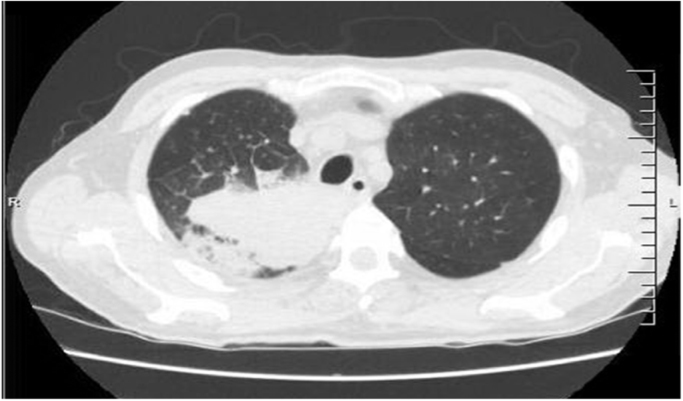

Computed tomography (CT) scan of the chest was performed on day 1 and demonstrated a large area of consolidation in the right upper lobe with a small area of cavitation with numerous lung nodules scattered throughout the lungs bilaterally (Fig. 1).

Fig. 1.

CT of the chest on admission to the hospital.